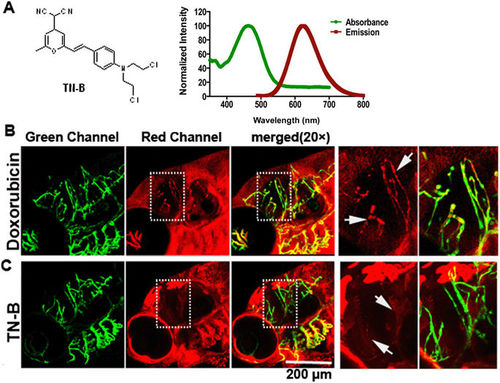

TN-B is capable of crossing the zebrafish BBB efficiently. Doxorubicin (Adriamycin�) and TN-B were injected into the circulation of 6dpf flk:eGFP zebrafish through caudal vein. Living images were obtained about 30?min after injection. (A) The structure of Nitrogen mustard based TN-B (left panel, A). The absorbance spectrum (green bold line) and emission spectrum (red bold line) of TN-B are shown (right panel, A). (B) Doxorubicin (Red Fluorescence) was completely restrained in cerebral capillaries, area in dotted box was magnified right, Doxorubicin was restrained in cerebral capillaries (arrows in B). (C) TN-B (showing with red fluorescence) readily penetrated the BBB into the brain parechyma, areas in dotted boxes were magnified right, TN-B crossing the cerebral capillaries into brain tissue (arrows in C). EXPRESSION / LABELING: